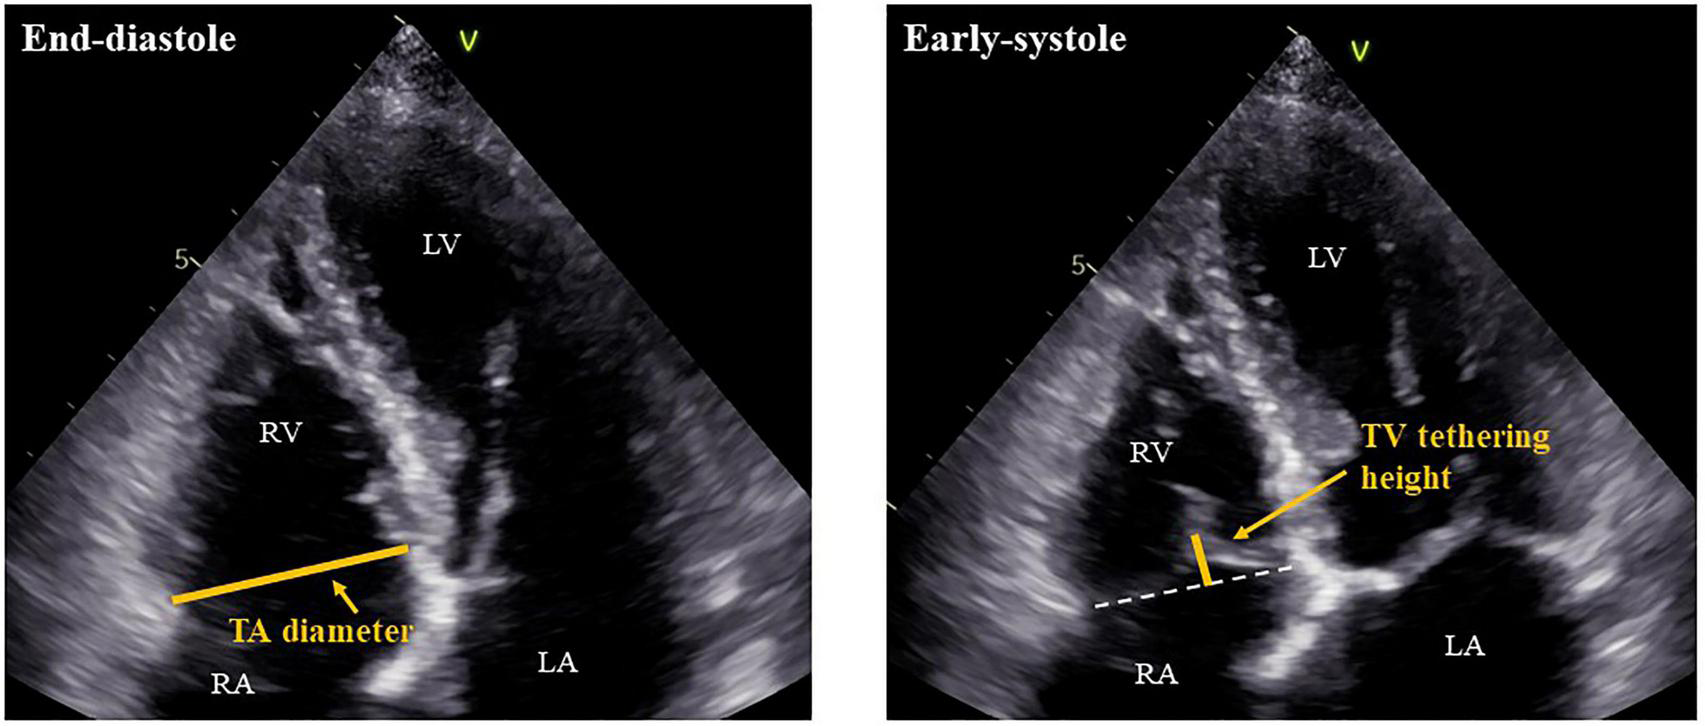

Patients in AF rhythm underwent 2-dimensional and Doppler echocardiography by experienced operators in accordance with the guidelines of the American Society of Echocardiography (14). Our echocardiography laboratory is maintained according to the guidelines of the Japanese Society of Echocardiography (15). LV volume was measured by disk summation in apical four-chamber and two-chamber views, and LVEF was evaluated by Simpson’s biplane method. When images of a two-chamber view were not appropriate for evaluation, we used only a four-chamber view to obtain LVEF. LV mass was calculated by the following formula: LV mass (g) = 0.8 × {1.04 × [(IVST + LV EDD + PWT)3 – (LVEDD)3]} + 0.6, where IVST is interventricular septum thickness, LV EDD is LV end-diastolic diameter, and PWT is posterior wall thickness (14). LV mass was divided by body surface area (BSA) to create LV mass index. We used pulse-wave Doppler echocardiography in the apical four-chamber view to assess early diastolic transmitral flow velocity (E). The early diastolic peak tissue Doppler imaging velocity (e’) was measured at the septal and lateral annulus sites in the apical four-chamber view and was averaged. The ratio of the E-wave to the mean e’ velocity (E/e’) was calculated to evaluate LV filling pressure (16). Left atrial (LA) volume was calculated from the apical four-chamber and two-chamber views using Simpson’s biplane method. When that was not possible, LA volume was measured only from the four-chamber view. LA volume was then indexed to BSA. RV and RA areas as well as TA diameter, TV tethering height, and TV tethering area were obtained from the RV-focused apical four-chamber view (17). TA diameter was measured at end diastole, while TV tethering height and area were measured at early systole (Figure 2). For assessing the reproducibility of echocardiographic measurements of TA diameter, TV tethering height, and TV tethering area, two independent observers repeated the measurements subsequently in 10 cases, and intraclass correlation coefficients (ICC) were calculated.

FIGURE 2

Measurements of TA diameter and TV tethering height. RV, right ventricle; RA, right atrium; LV, left ventricle; LA, left atrium; TA, tricuspid annulus; and TV, tricuspid valve.